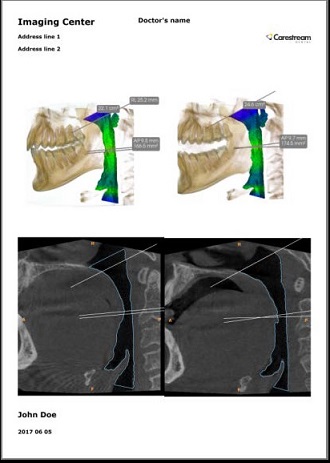

Condivisione e stampa versatile

Tutte le immagini e le misurazioni possono essere salvate sotto forma di istantanee dello schermo (screenshot), ed essere poi stampate per la condivisione con pazienti, medici richiedenti o enti assicurativi. Inoltre, è possibile condividere con i pazienti immagini pre-trattamento e post-trattamento per aiutarli a visualizzare i benefici del trattamento.